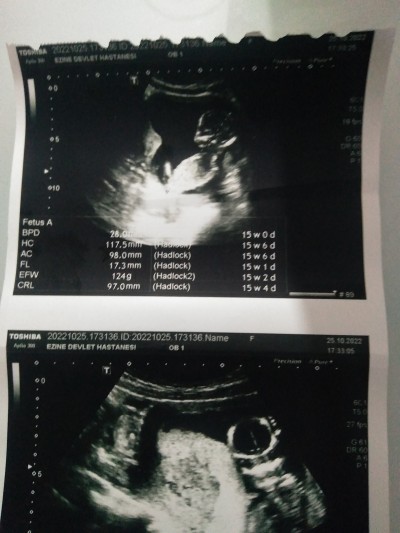

15+5 haftalık hamileyim daha doktor kontrolüme var sizden bi tahmin alabilirmiyiz önce kıza benziyor dedi sonra pipisi var dedi ve kararsız kaldı doktor

image